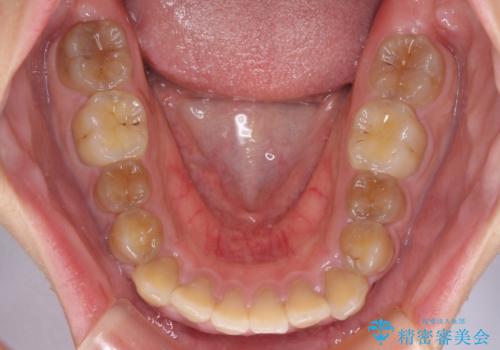

- 口元の突出感を気にして来院された患者様です。

上下前歯が著しく前突している状態であったので、上下左右の第1小臼歯4本を抜歯し、ワイヤー装置にて矯正治療を行うこととしました。

舌の突出癖により、前突になったと考えられたため、舌のトレーニングをしっかりと行うよう指導しました。